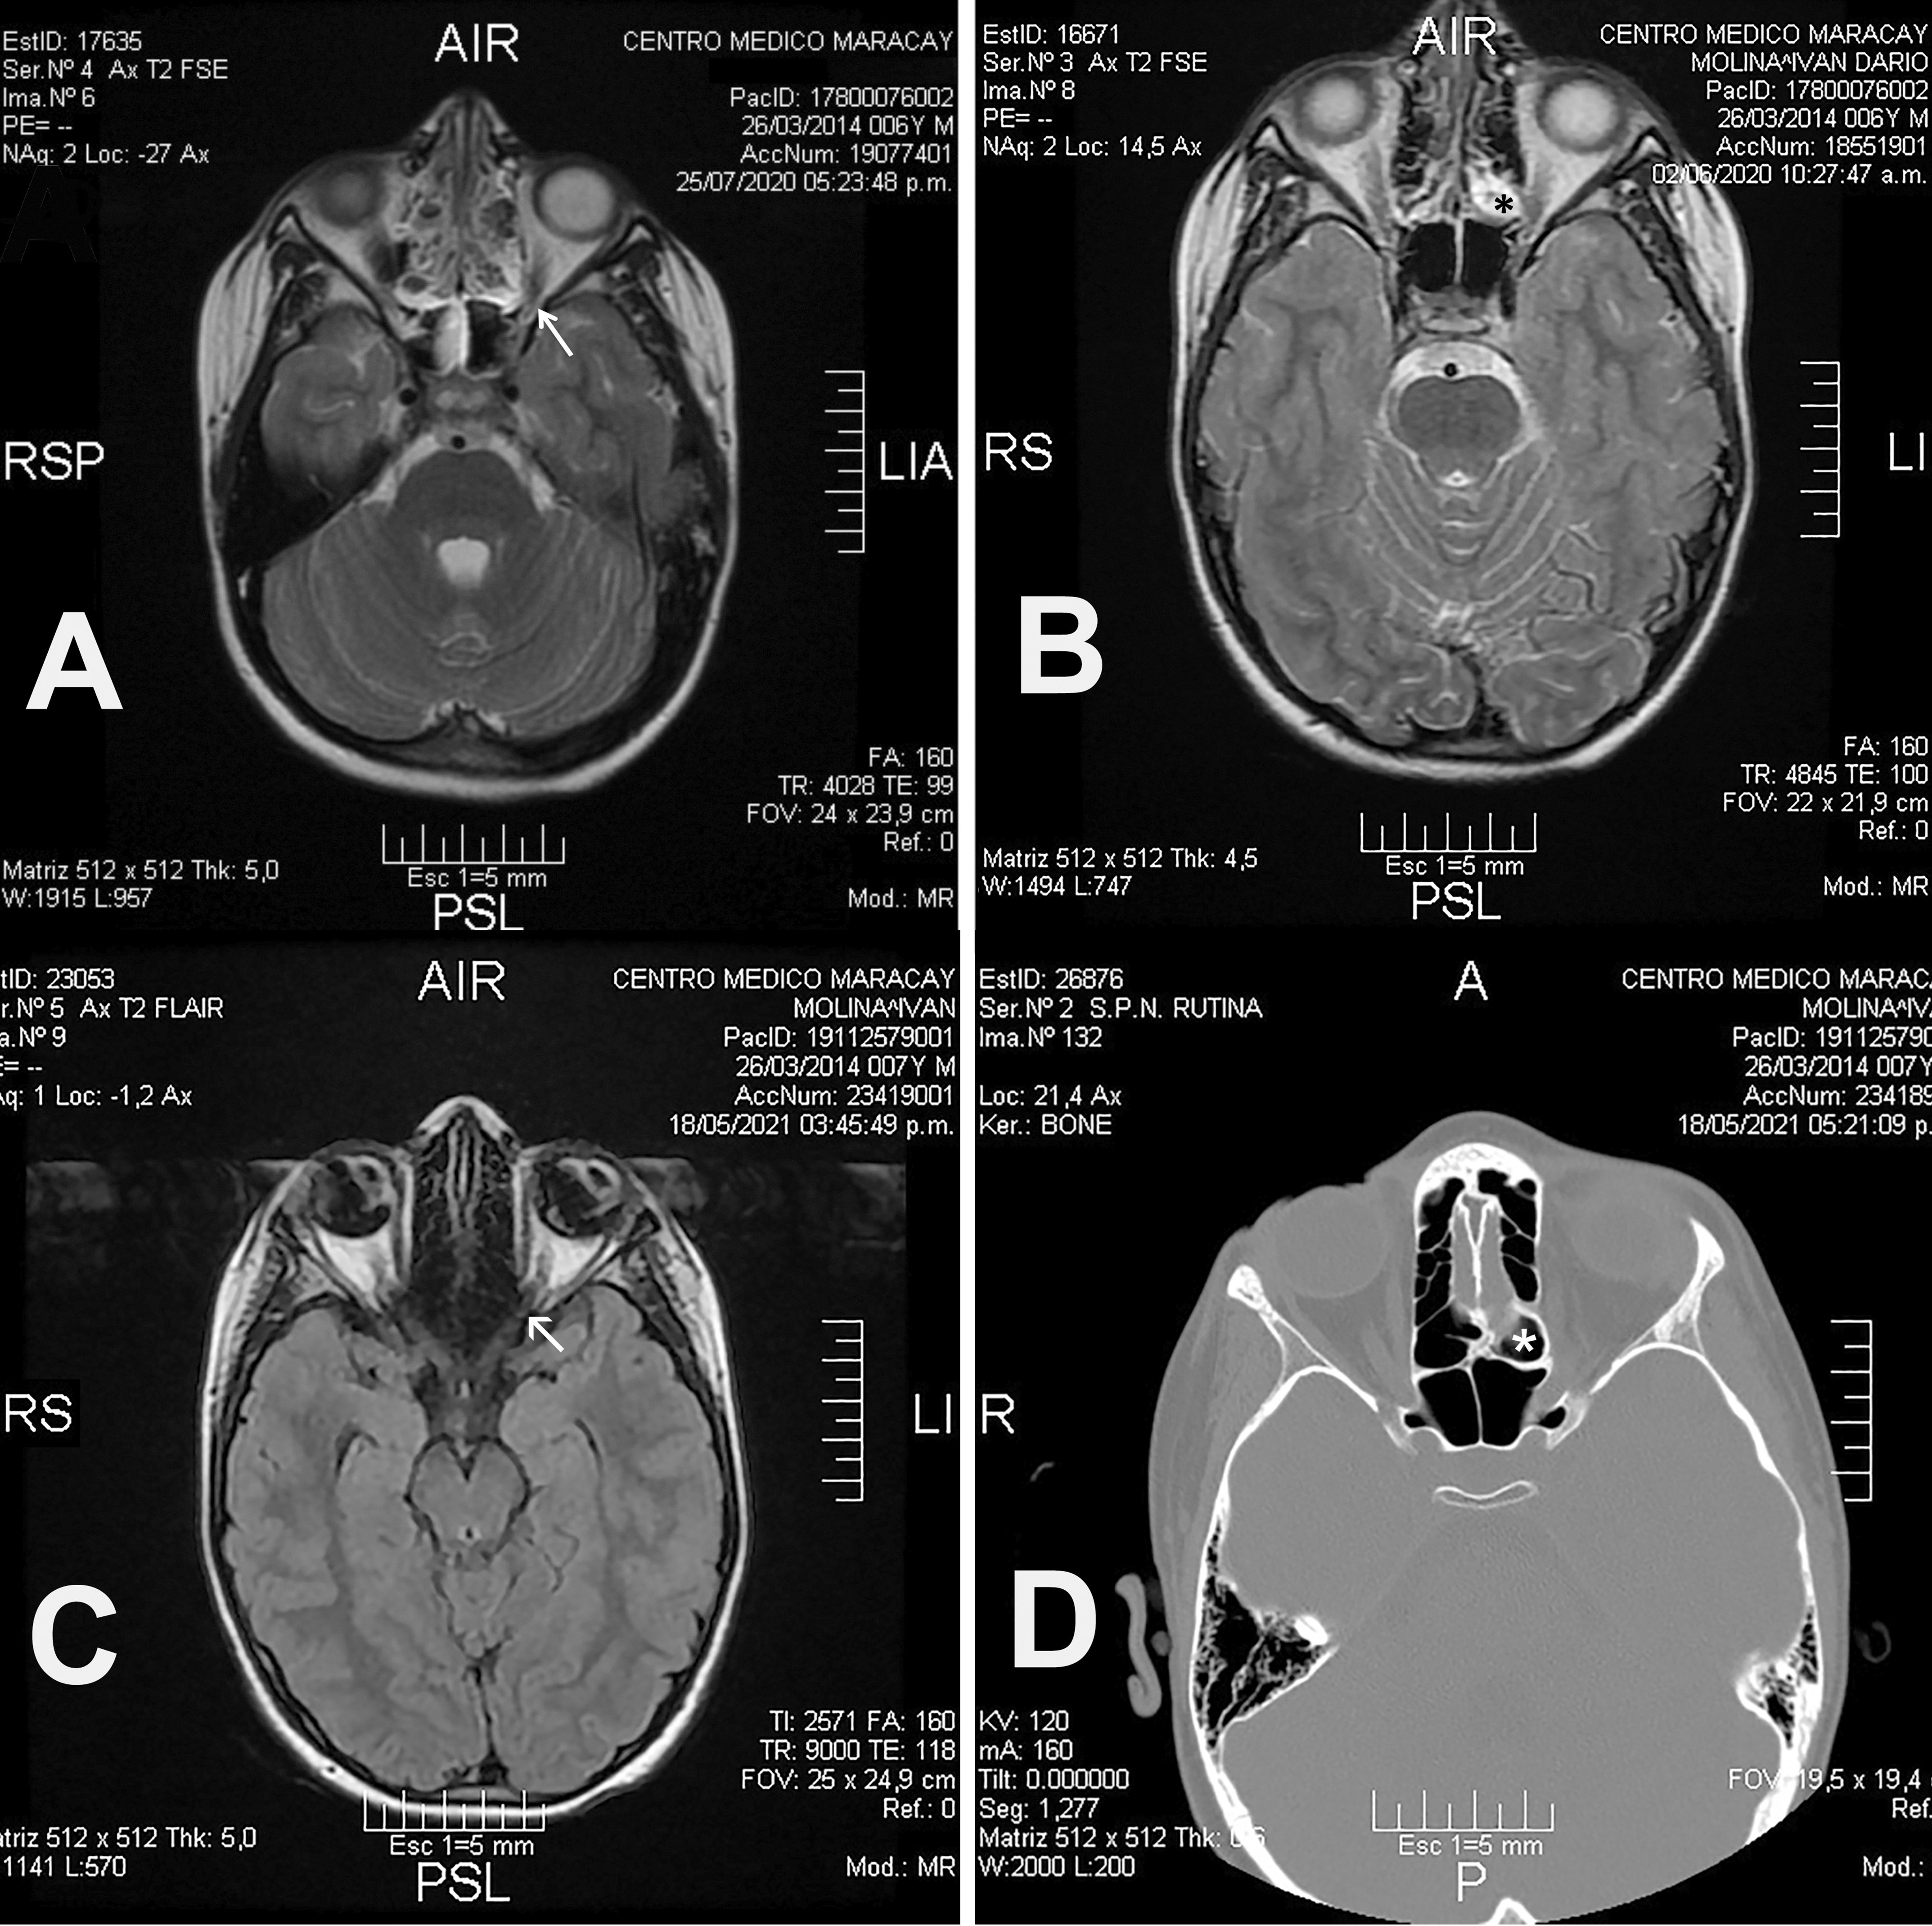

El estudio de Resonancia Magnética Nuclear (RMN) mostraron en imágenes ponderadas en T1 y T2 con evidencia de señal hiperintensa, ocupando todo el seno etmoidal posterior izquierdo, extendiéndose a la pared orbitaria a nivel de su ápex orbitario [Figura 1A], con un estrecho contacto con el segmento intracanalicular del nervio óptico izquierdo. [Figura 1B]

La mejoría clínica se demostró en el seguimiento con RMN y TCSPN, evidenciándose una importante regresión y franca tendencia a la resolución de los hallazgos inicialmente observados. [Figuras 1C y 1D]

Figura 1.

En algunos casos una CEE muy neumatizada puede observarse en estudios de TC, dentro del seno Esfenoidal. (9). Ver la figura 1.